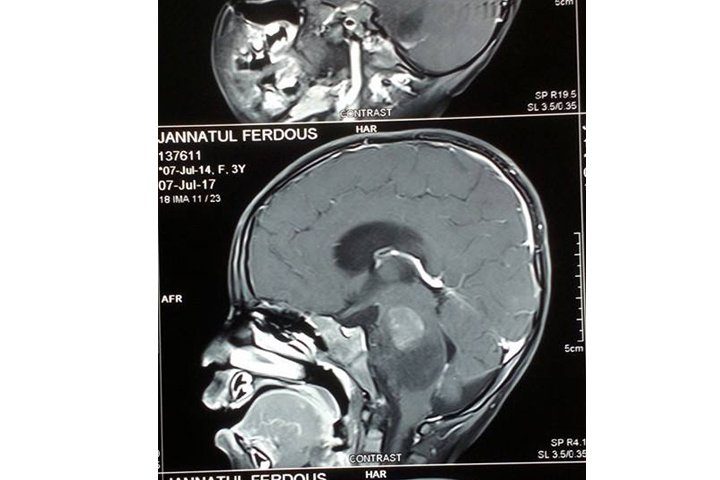

চট্টগ্রামের সন্দ্বীপ উপজেলার বাউরিয়া পৌরসভার ৬ নং ওয়ার্ডের ওয়াসিম ওসমান ও নাসরিন সুলতানার আদরের ছোট মেয়ে জান্নাতুল ফেরদৌস। যে শিশু এখনো পৃথিবী সম্পর্কে সম্যক ধারণা নেই, অথচ বাবা-মা কে প্রায়শ বলে বড় হলে ডাক্তার হবে।সেই স্বপ্ন জাগানিয়া মোহনীয় হাসির অধিকারী শিশু জান্নাত এখন ব্রেন টিউমারে আক্রান্ত হয়ে রাজধানীর বঙ্গবন্ধু শেখ মুজিব মেডিকেল বিশ্ববিদ্যালয়ের বিছানায় অসহায় হয়ে জীবন মৃত্যুর সন্ধিক্ষণে দিন কাটাচ্ছে।

তিন বছর বয়সী শিশু জান্নাত যে বয়সে মায়ের কোলে থাকার কথা,সে বয়সে নিয়তি অনিশ্চিত করে দিয়েছে তাঁর জীবন। এবছরের মে মাসে তার ব্রেন টিউমার ধরা পরে। চট্টগ্রামের ‘আগ্রাবাদ মা ও শিশু হাসপাতালে’ তার প্রাথমিক রোগ ধরা পরে। এছাড়া তাকে মেক্স হাসপাতাল, সিএসসিআর ও চট্টগ্রাম মেডিকেল কলেজ ও হাসপাতালে চিকিৎসা দেওয়া হয়।

জান্নাতের চিকিৎসা সম্পর্কে অধ্যাপক ধীমান চৌধুরী জানিয়েছেন, জান্নাতের অপারেশন এখানে সম্ভব নয়। কারণ ওর টিউমারটা ব্রেনের টিস্যুর ভিতরে ছড়িয়ে পড়েছে। উন্নত চিকিৎসার জন্য দ্রুত দেশের বাহিরে নিতে হবে। এ ধরনের জটিল টিউমারের সঠিক চিকিৎসার জন্য সিঙ্গাপুরের মাউন্ট এলিজাবেথ অথবা বেঙ্গালুর সিএমসি যাবার পরামর্শ দিয়েছেন তিনি।